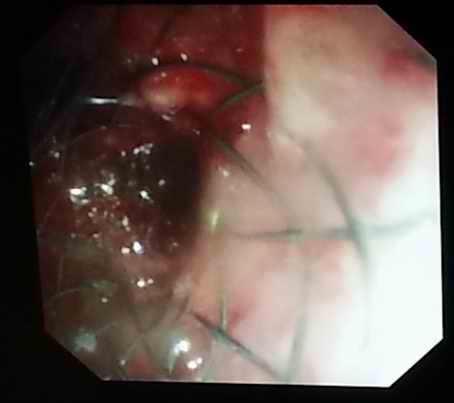

今日,我科为一肿瘤晚期患者成功进行了Y型支架植入术。该患者为肺癌晚期患者,经多次放化疗,效果不佳,肿瘤严重阻塞患者气管,支气管,危及生命。我科经过会诊,决定给予Y型支架植入术缓解患者症状,挽救患者生命。患者全麻下,由俞万钧副院长主刀,经历半小时,成功放置Y型支架,患者术后症状明显缓解,生活质量大大提高。我科已多次为肿瘤晚期患者行Y型支架植入术(徐涛)

图片2